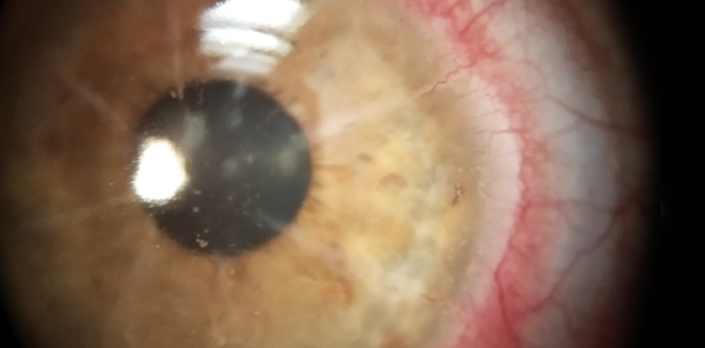

Se trata de una paciente de 28 años de edad quien acude a consulta de optometría por presentar disminución de su agudeza visual e incomodidad con sus lentes de contacto habituales. Al hacer la anamnesis informa que le realizaron cirugía Lasik a los 15 años de edad....